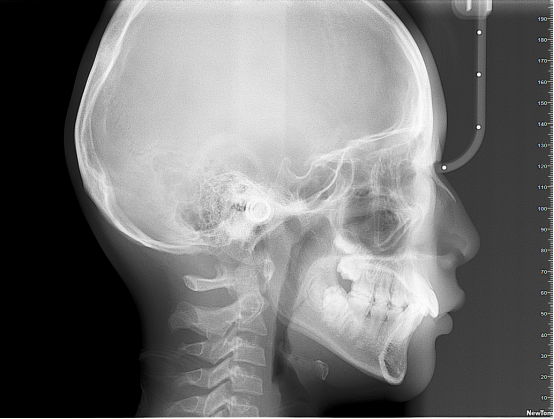

正畸通过扫描形成图像,包括曲面体层、头颅侧位进行测量图像。2D和3D图像在确定多生牙的存在及位置方面,有着巨大的差别。3D图像对扫描区域有着完整,综合的展示,甚至允许通过不同视角,以及对不同断面重建图像进行观察。